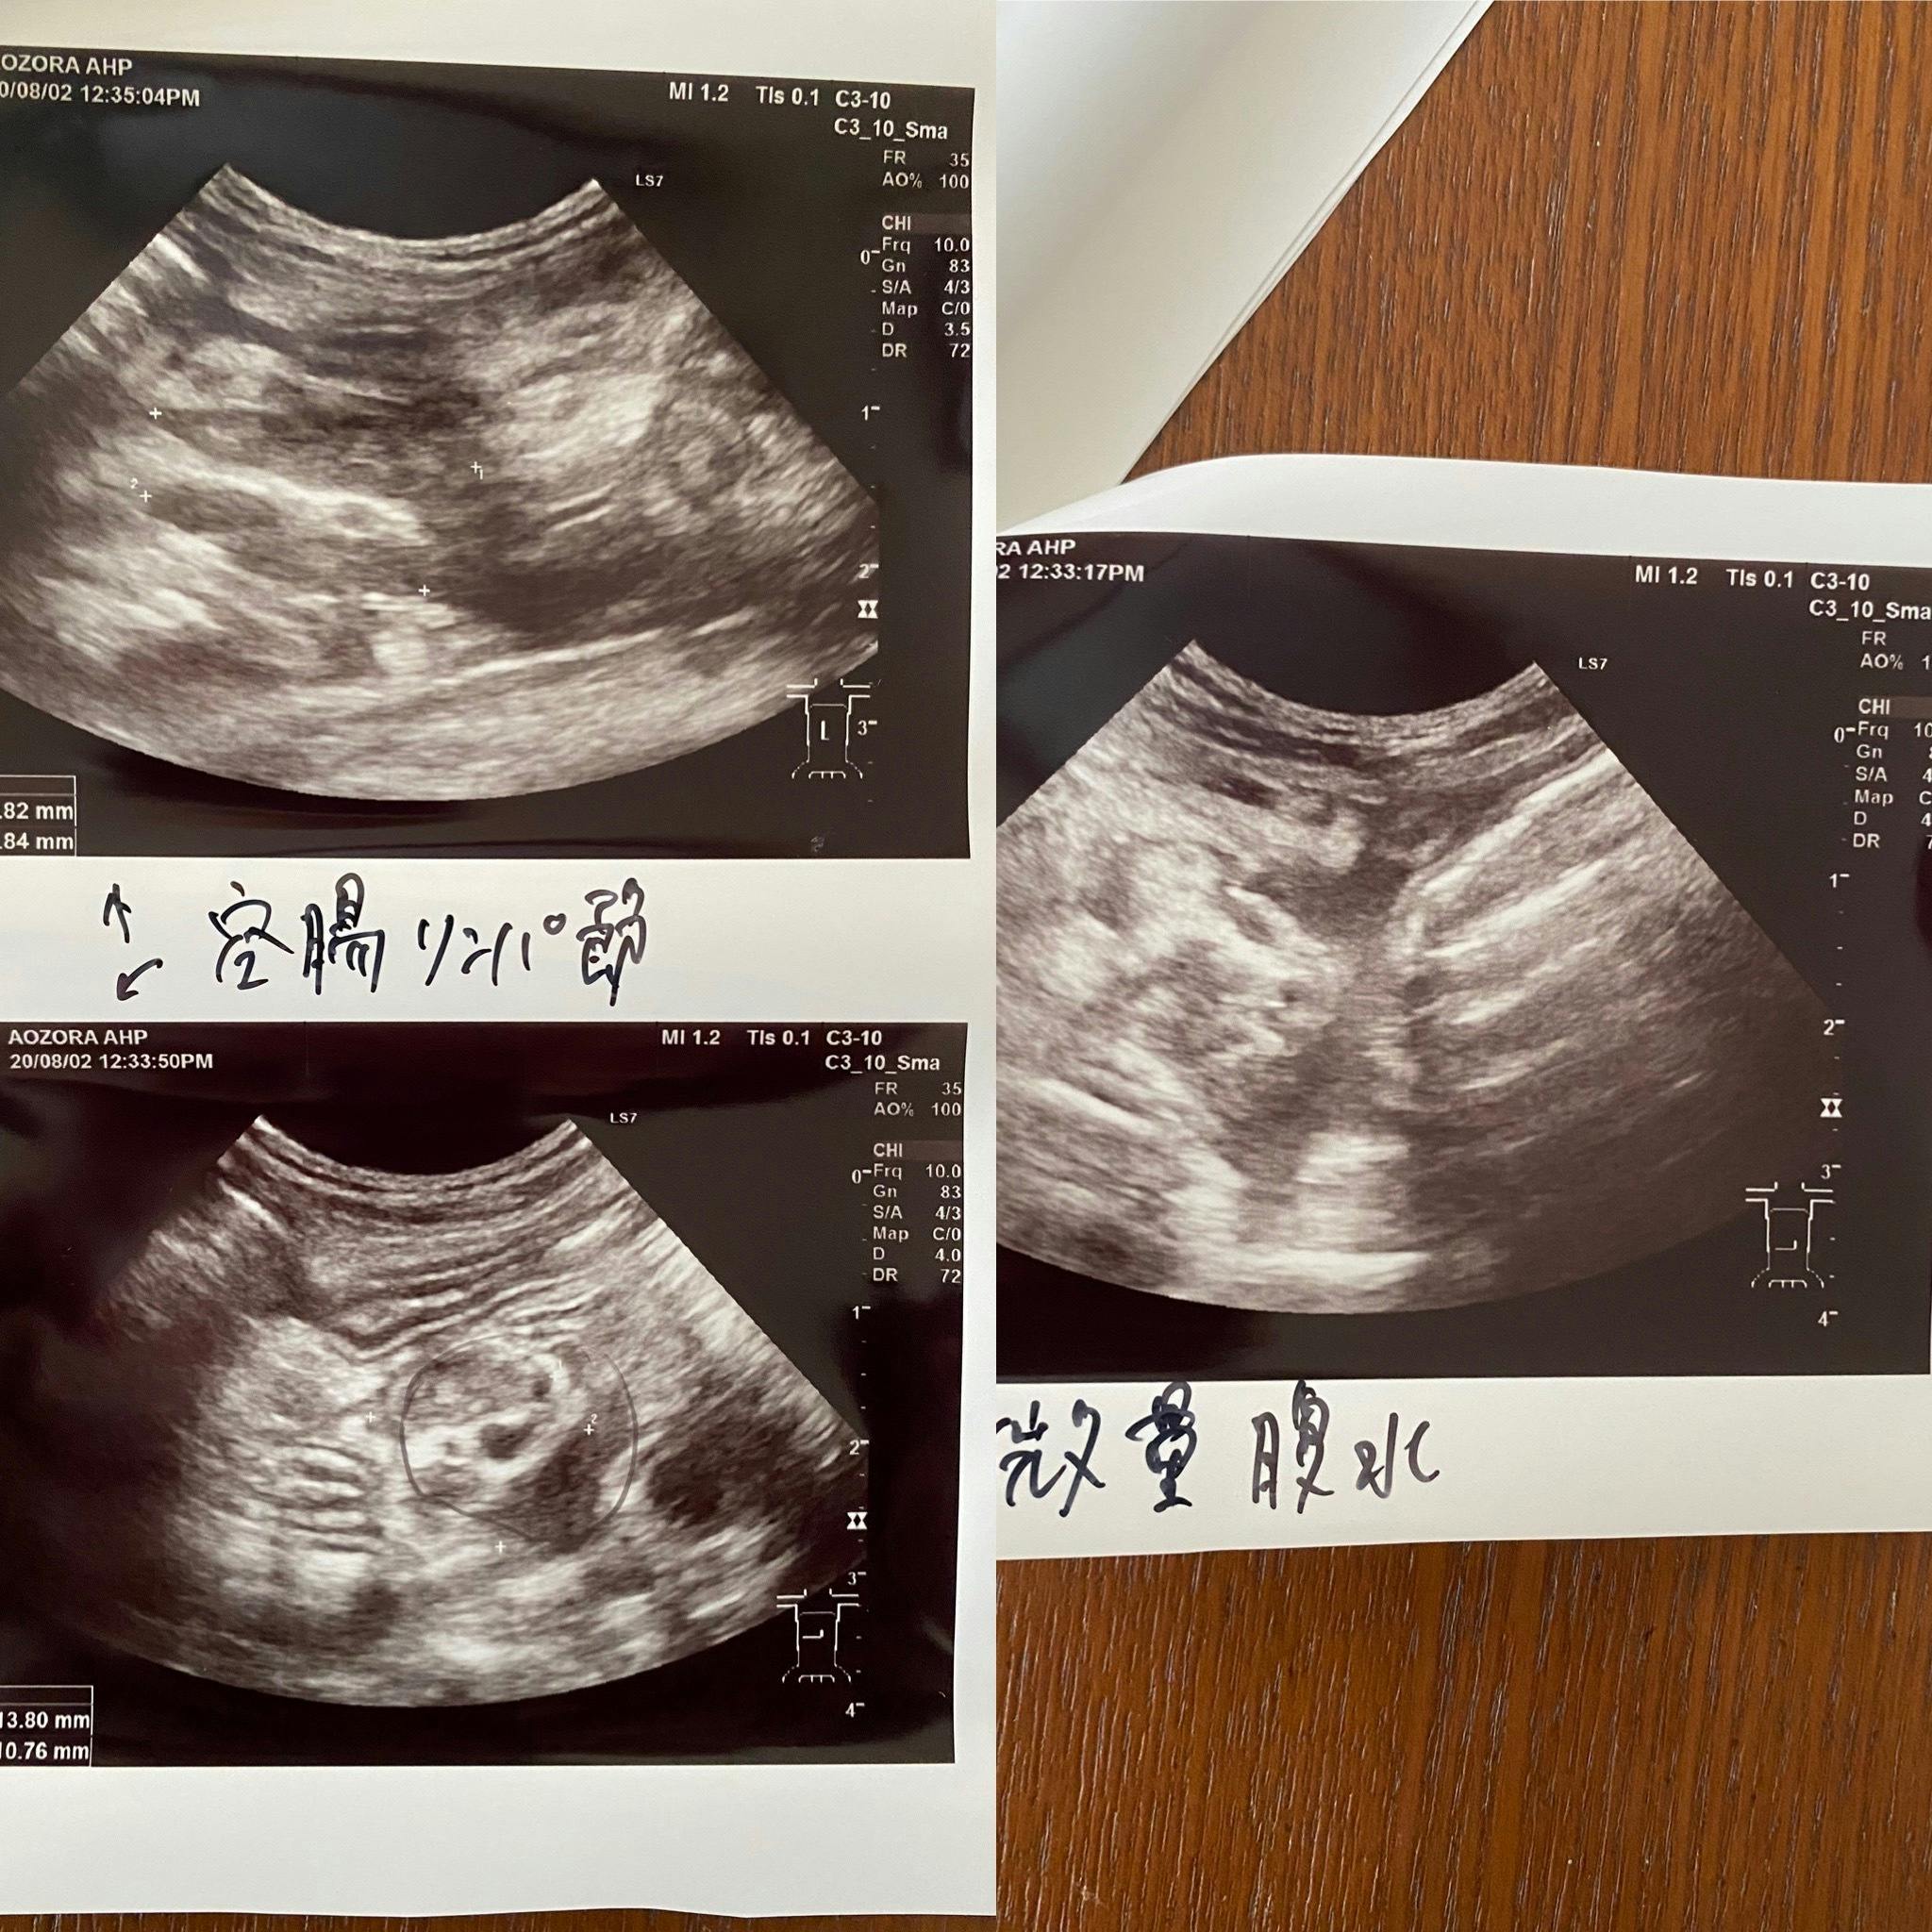

検査入院中のテオ

実は7年前に生後5ヶ月の子猫をこのFIPで亡くし非常に辛い思いをしました。そして今回のテオです。何とか治療を受けさせ治してあげたいと思い、色々と調べました。なんと偶然にも同じ市内にこのサプリメントの協力病院があるのを知りました。すぐに病院に電話し診察をして頂きました。結果はFIP混合型でした(FIPには3種類あり①ウエットタイプ②ドライタイプそして①②の混合型があります)。そして黄疸も出ており肝臓も良くないとの事でした。